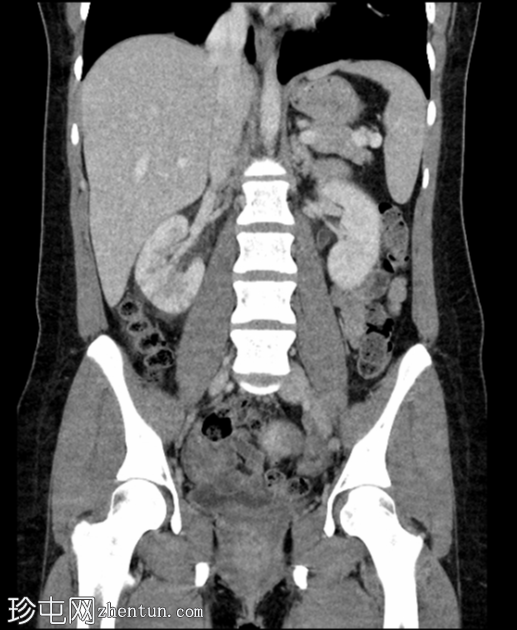

冠状位增强扫描(门静脉期)

右肾在轴位和冠状位图像上均可见多个楔形低强化区,伴有轻度肾周脂肪间隙模糊。

双侧肾盂及输尿管轻度壁增厚和强化。

膀胱壁轻度增厚。

影像

学表现提示右侧急性肾盂肾炎和左侧肾盂及输尿管炎。